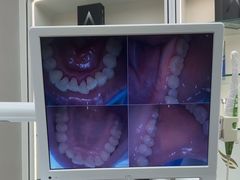

• -牙博士口腔品牌连锁(杨浦店)

【已注销用户】 | 24-06-27

报错